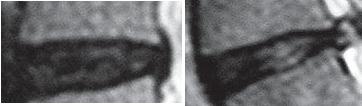

На МРТ № 132 и МРТ № 133 — увеличенные фрагменты МРТ № 130 межпозвонковых дисков в сегментах LIV-LV и LV—SI до лечения методом вертеброревитологии. Структура межпозвонковых дисков неоднородна.

На МРТ № 134 и МРТ № 135 — увеличенные фрагменты МРТ № 131 межпозвонковых дисков в сегментах LIV-LV и LV—SI, после лечения методом вертеброревитологии.

Наблюдается весьма интересное явление — репаративная регенерация. Обратите внимание, насколько уменьшилось количество некрозной (мёртвой) ткани и увеличилось функциональной (живой) ткани. Примечательно, что хондроциты при регенерации в данной фазе формируют вертикальные и наклонные «колонны» согласно вектору нагрузки на межпозвонковый диск в районе фиброзного кольца. В центре межпозвонкового диска наблюдается не менее интересное явление — начало регенерации пульпозного ядра!